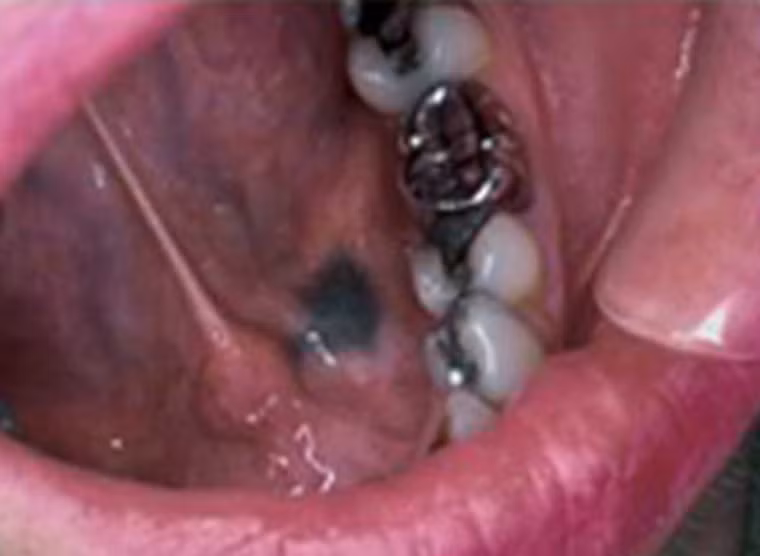

Còn đây là khoang miệng người phụ nữ 31 tuổi vừa được chẩn đoán mắc ung thư. Răng cùng một số mô xung quanh chuyển sang màu đen và có dấu hiệu di căn khá mạnh sang các tế bào khác.